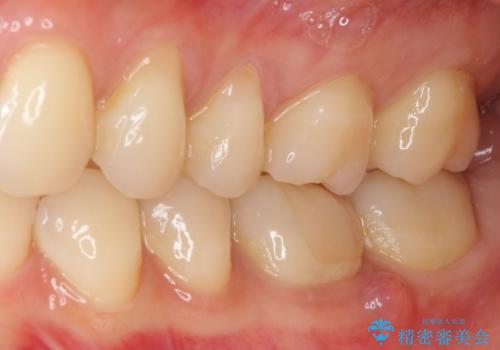

- 近医にてセラミックを装着した左下の奥歯に痛みが続いたとのことで来院された患者様です。

診査の結果、既に歯の神経は失活していたおり、排膿路が認められ、叩いたり触ったりしたときの痛みも確認されました。

根管治療を行った後にオールセラミッククラウンにて補綴することとしました。

初回の治療後には歯肉に認められた排膿の出口などの症状は消えていました。